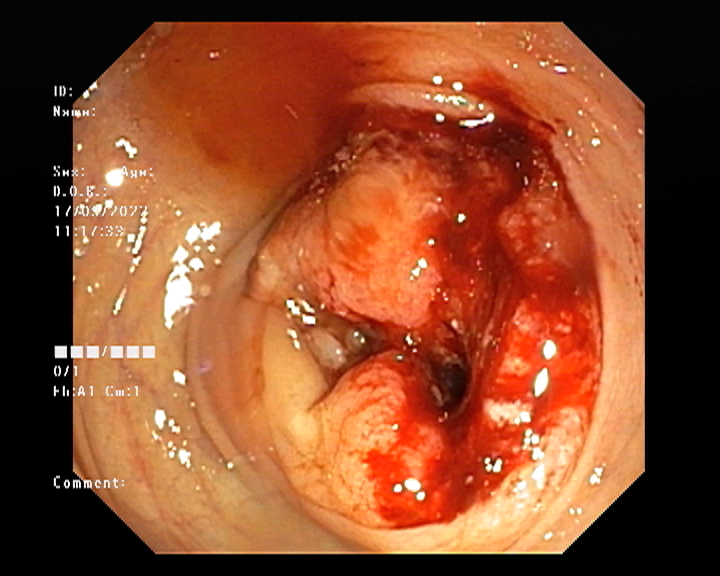

Endoscopy and colonoscopy are safe and accurate procedures used to directly examine the digestive tract and detect the root cause of chronic acidity, GERD, abdominal pain, bleeding, and bowel irregularities. These minimally invasive tests help identify ulcers, inflammation, infections, polyps, strictures, and early cancerous changes.

At Sapphire Gastroenterology Center, modern endoscopic equipment ensures precise diagnosis and, when required, therapeutic intervention during the same procedure. Based on findings, targeted treatment plans are created, including medication, diet guidance, and preventive strategies. Early diagnosis through endoscopy and colonoscopy plays a crucial role in preventing serious complications and improving long-term digestive health.